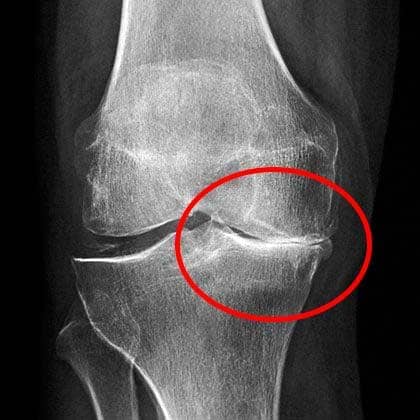

Moje koleno bilo je u neizdrživim bolovima.

Na pregledu su mi rekli da ne smem da dižem ništa teže od 2 kg. Kako da zadržim posao? Drugi lekar me je upozorio da ću, ako ne uradim operaciju, ostati radno nesposobna. Operacija je koštala 3.500 evra, što nisam imala.

Rendgen je pokazao ozbiljna oštećenja.

Ovako izgleda moje koleno danas.